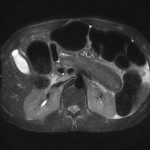

- T2